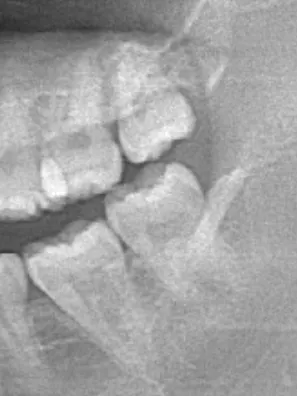

在醫師的展示下,拿著小鏡子的我,親眼看到我的後牙們咬合的時候不但沒有因為智齒的作用增加對咬的面積,反而因為智齒的生長害得隔壁牙齒咬不到對面。總之醫師建議拔掉。